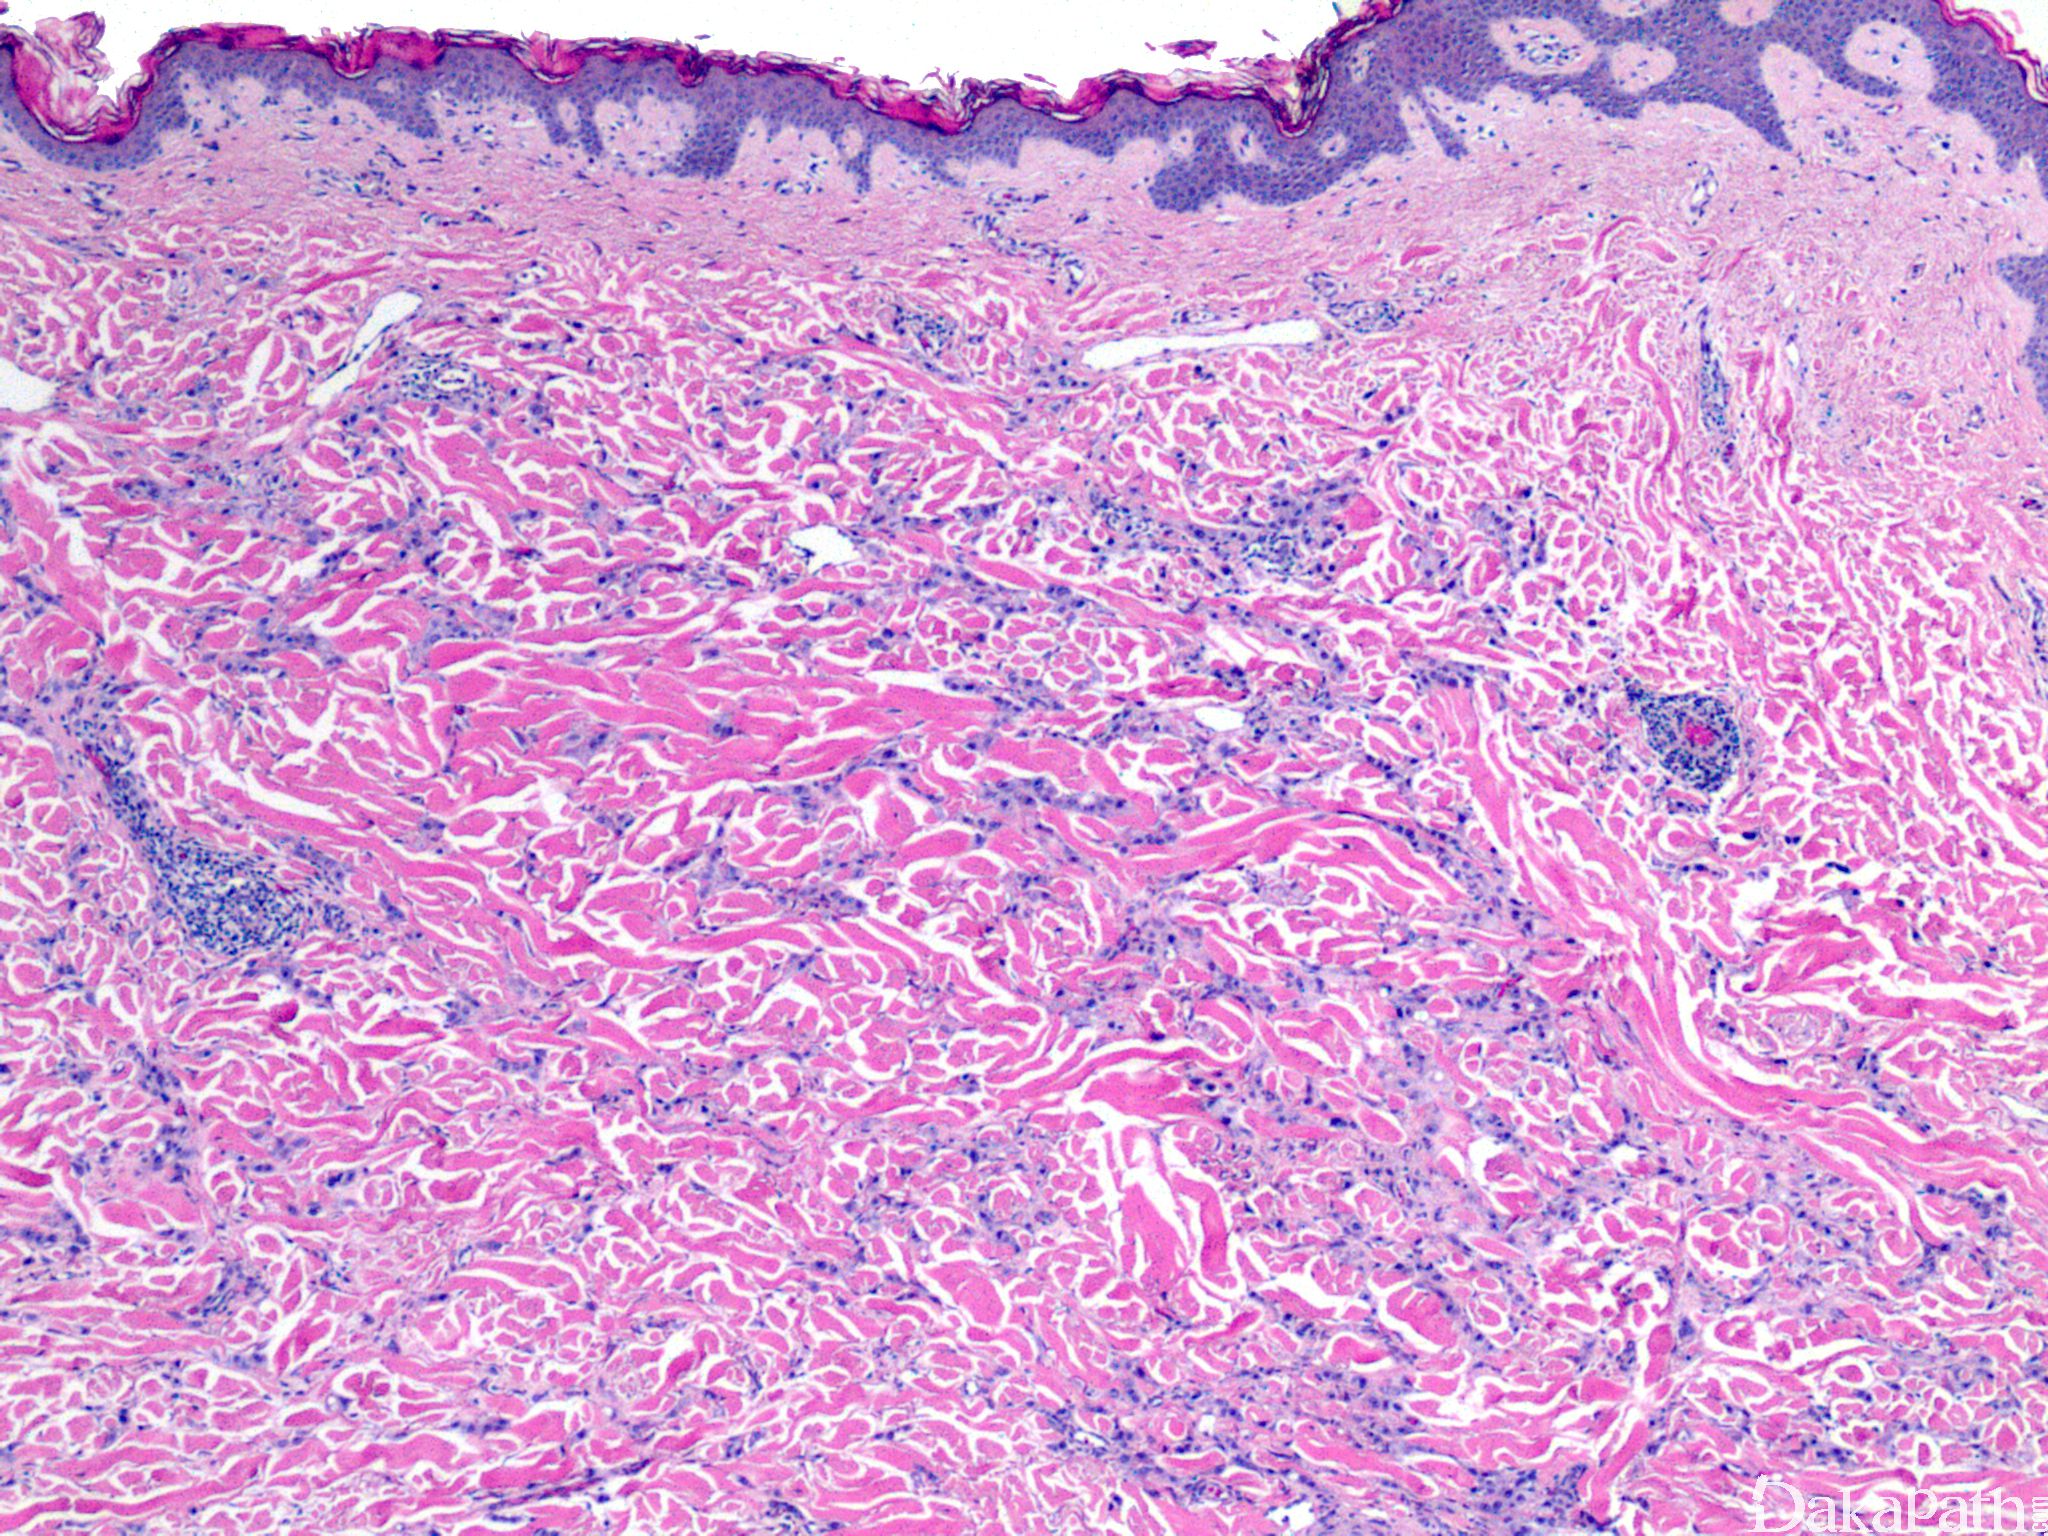

皮肤乳腺转移癌